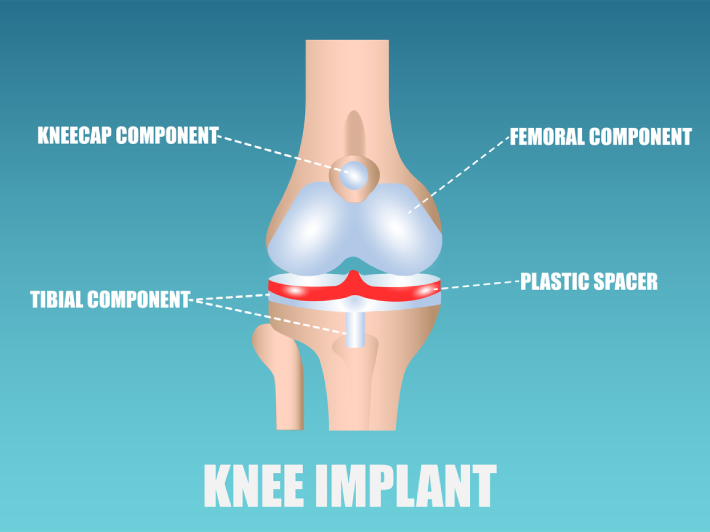

In simple terms, a knee replacement is a surgery performed to replace the original knee with an artificial joint. The implants are made of a combination of ceramic, metal and plastic materials.Usually, people suffering from osteoarthritis, arthritis, rheumatoid arthritis, developmental abnormalities, bone death, accidents or obesity are recommended such surgeries because it affects their daily life and mobility.

A total or partial knee replacement surgery can be performed depending on the condition of the patient. While performing a total knee replacement surgery, the bones in the femur, tibia and patella are resurfaced. A plastic cushion is often used to replace the cartilage between the tibia and femur bones.